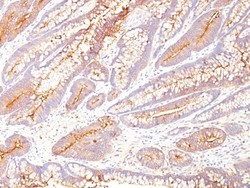

Supportive validation

- Submitted by

- Novus Biologicals (provider)

- Main image

- Experimental details

- Immunohistochemistry-Paraffin: CEACAM5/CD66e Antibody (SPM584) - Azide and BSA Free [NBP2-34851] - Immunohistochemistry-Paraffin: CEA Antibody (COL-1) [Azide Free] - Staining of colon carcinoma.